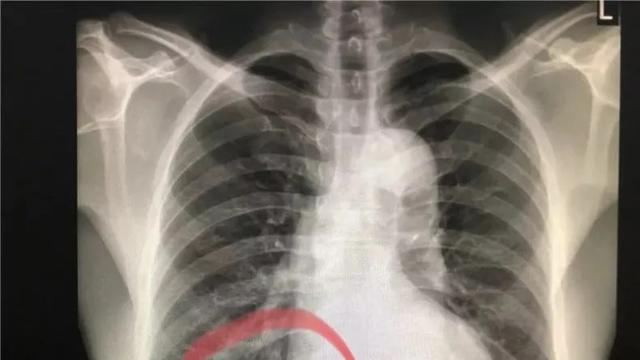

Meskipun operasi ini bukan tanpa risiko, dengan kehati-hatian yang ekstra dan keahlian medis yang tinggi, tim berhasil menyingkirkan paku tanpa menimbulkan masalah yang lebih serius. Hasil dari rontgen yang dilakukan setelah operasi menunjukkan dengan jelas paku yang menonjol di tenggorokan Tello.